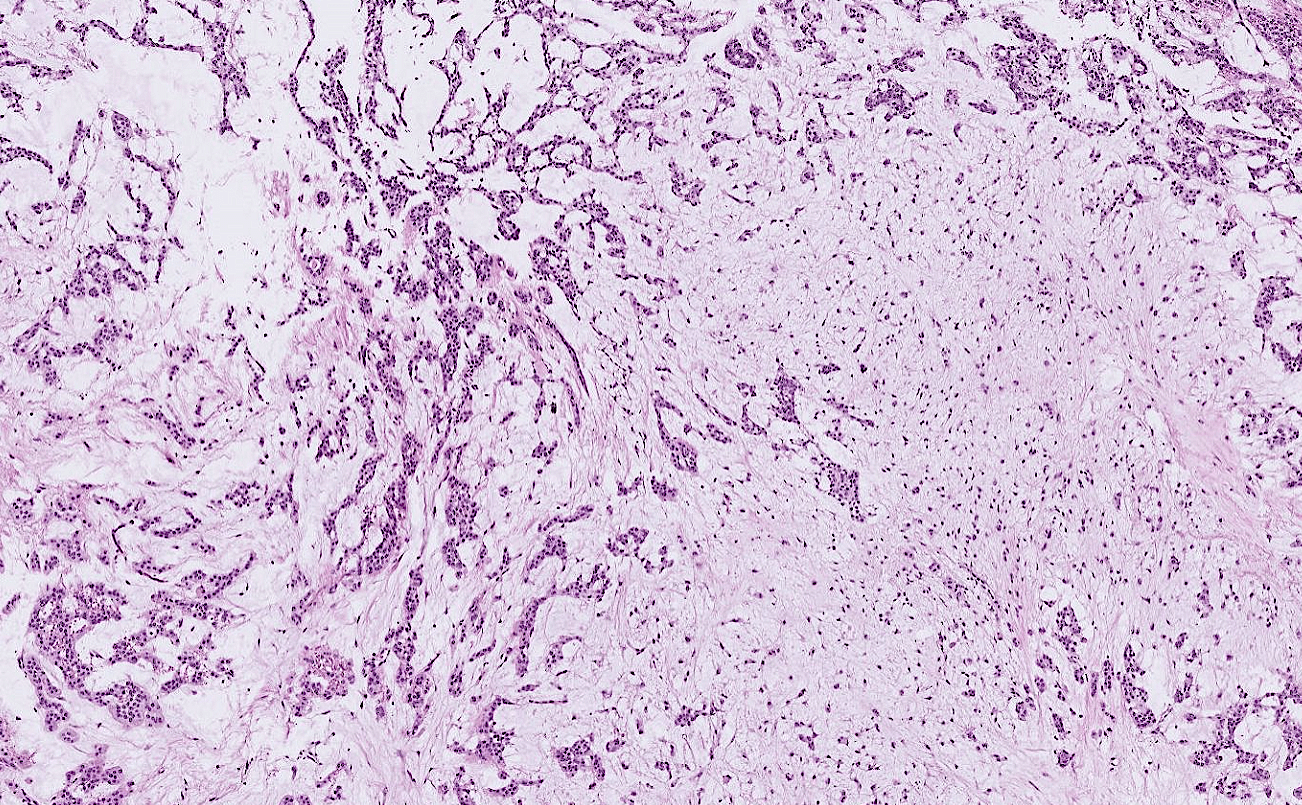

lung adenocarcinoma

colon cancer

endometrial cancer